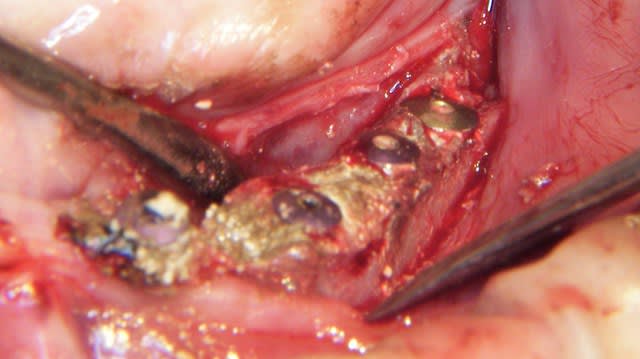

un cas que je ne retrouvais plus, et puis wikileaks l'a publié (les enfoirés c'était ultra-secret)

le Vitalos sur les photos, ça fait bien crade !

Cela dit, c'est p'être bien un excellent biomat' que je ne connais qu'à travers tes iconographies

L'expansion pour gagner 1 à 2 mm c'est très sympa, j'y ai souvent recours au maxillaire

Le cas que tu montre est extrême et pas vraiment fastoche:

DI à la mandibule en zone symphysaire, c'est le plus dur non ?.

Le côté "facilitateur" c'est la grande étendue